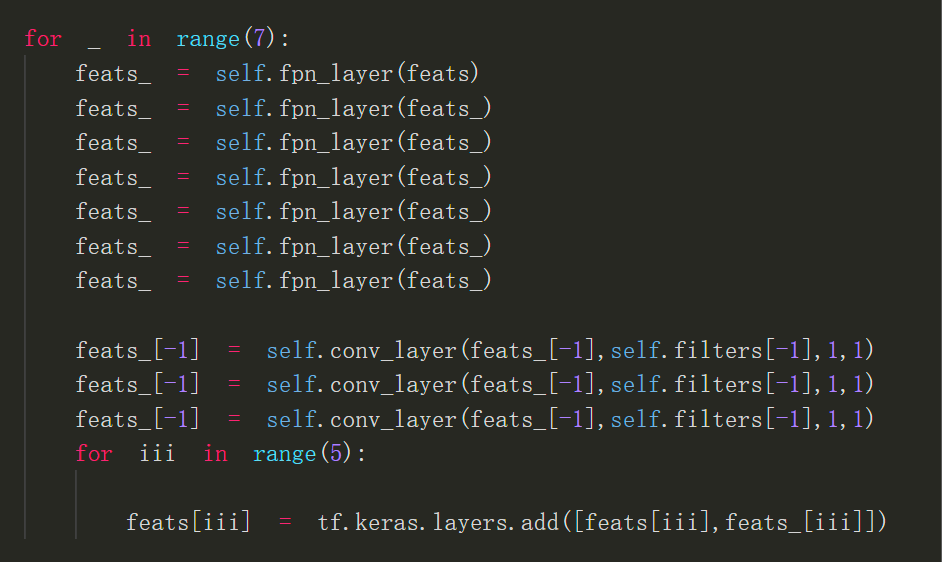

ResFPN关键代码

输出头部分的第一个conv 为继续下采样到32x32,第二个conv为调整最后的输出,比如将loc的输出filter调整为2,中间置一个dense net为防止过拟合(dense net之间的每个连接分别加一层0.5的dropout)

以上便是我此次参加比赛所使用的模型,提交分数为0.633,但此模型其实还可以做些改进,比如将backbone出来的feats继续下采样的resnet换成efficientnet block,ResFPN也可以继续改进到ResFPN2.0,ResFPN里的每层fpn_layer其实就是一次自顶向下融合,ResFPN2.0与第一代ResFPN的区别就是ResFPN2.0每一次自顶向下融合之后最顶上的特征图就进行一次卷积之后再进行下一次融合。

以下是ResFPN2.0关键代码: